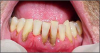

Stain & Calculus: While saliva flow is generally reduced in chronic smokers, the act of smoking stimulates serous saliva flow. This can increase calculus production. Stain is generally present. The combination of stain and calculus may compromise the periodontal health of most smokers.

Gingival and Periodontal Diseases: Conditions such as necrotizing ulcerative gingivitis (NUG) is prevalent in smokers. Scientific evidence clearly shows smokers have more severe periodontal diseases than do non-smokers. Continued smoking is likely to compromise the success of periodontal therapy. More refractory periodontal patients are smokers (90%) when compared to the general population (25%).

Additional Oral Changes: Smokers may also experience candidiasis, nicotine stomatitis, smoker's keratosis, pigmentation changes, and xerostomia (Figure 2).